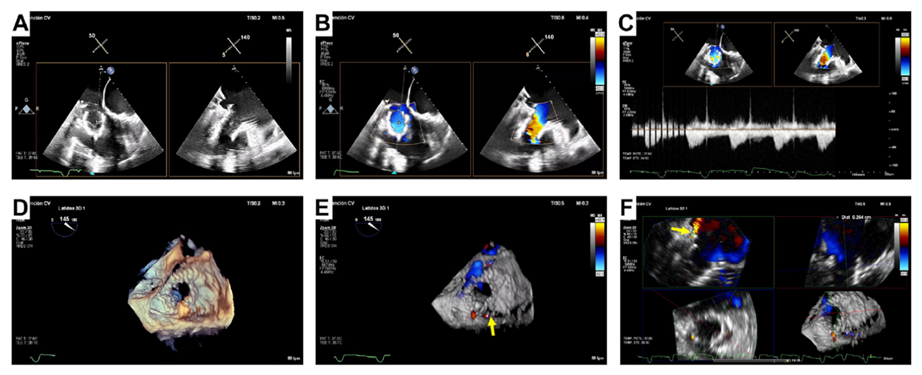

基線經胸和經食道超聲

術后經食道超聲,僅微量瓣周漏